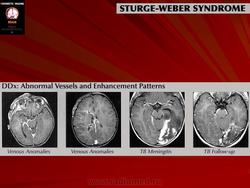

Синдром Sturge-Weber.

Синдром Sturge-Weber.

Синдром Sturge-Weber.

Синдром Sturge-Weber.

Синдром Sturge-Weber.